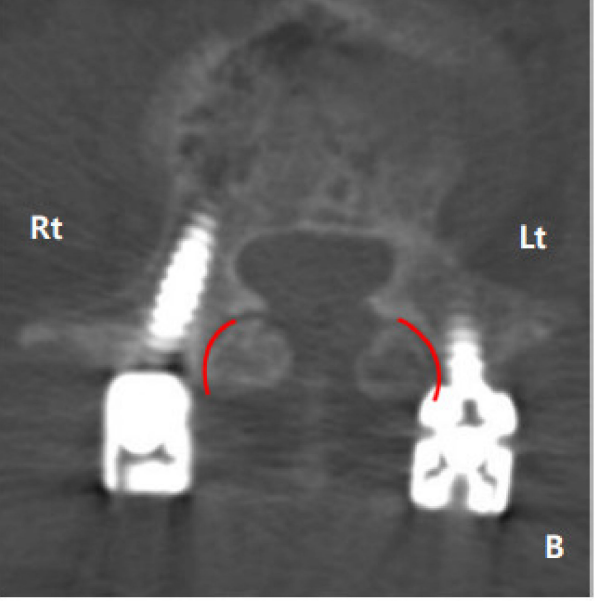

4.Seo分级

0级:螺钉明显避开关节

1级:螺钉接触或疑似已侵入关节

2级:螺钉明显破坏关节

左侧1级,右侧2级

左侧1级,右侧0级